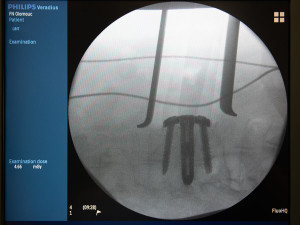

Implantát podle daných parametrů vyrábí čínská firma, v České republice jej využívají ve fakultních nemocnicích v Olomouci a v Ostravě. Náhrada ploténky je konstruována tak, že se do meziobratlového prostoru při operaci dostane šetrně. „Stabilita je zajištěna takzvanou distrakcí, kdy se implantát v meziobratlovém prostoru roztáhne na výšku až o 4 milimetry, a tím pevně drží. Navíc je integrovanou součástí XLIF Lumir cage i dlaha s možností fixace implantátu do obratlových těl čtyřmi šrouby,“ dodává profesor Hrabálek.